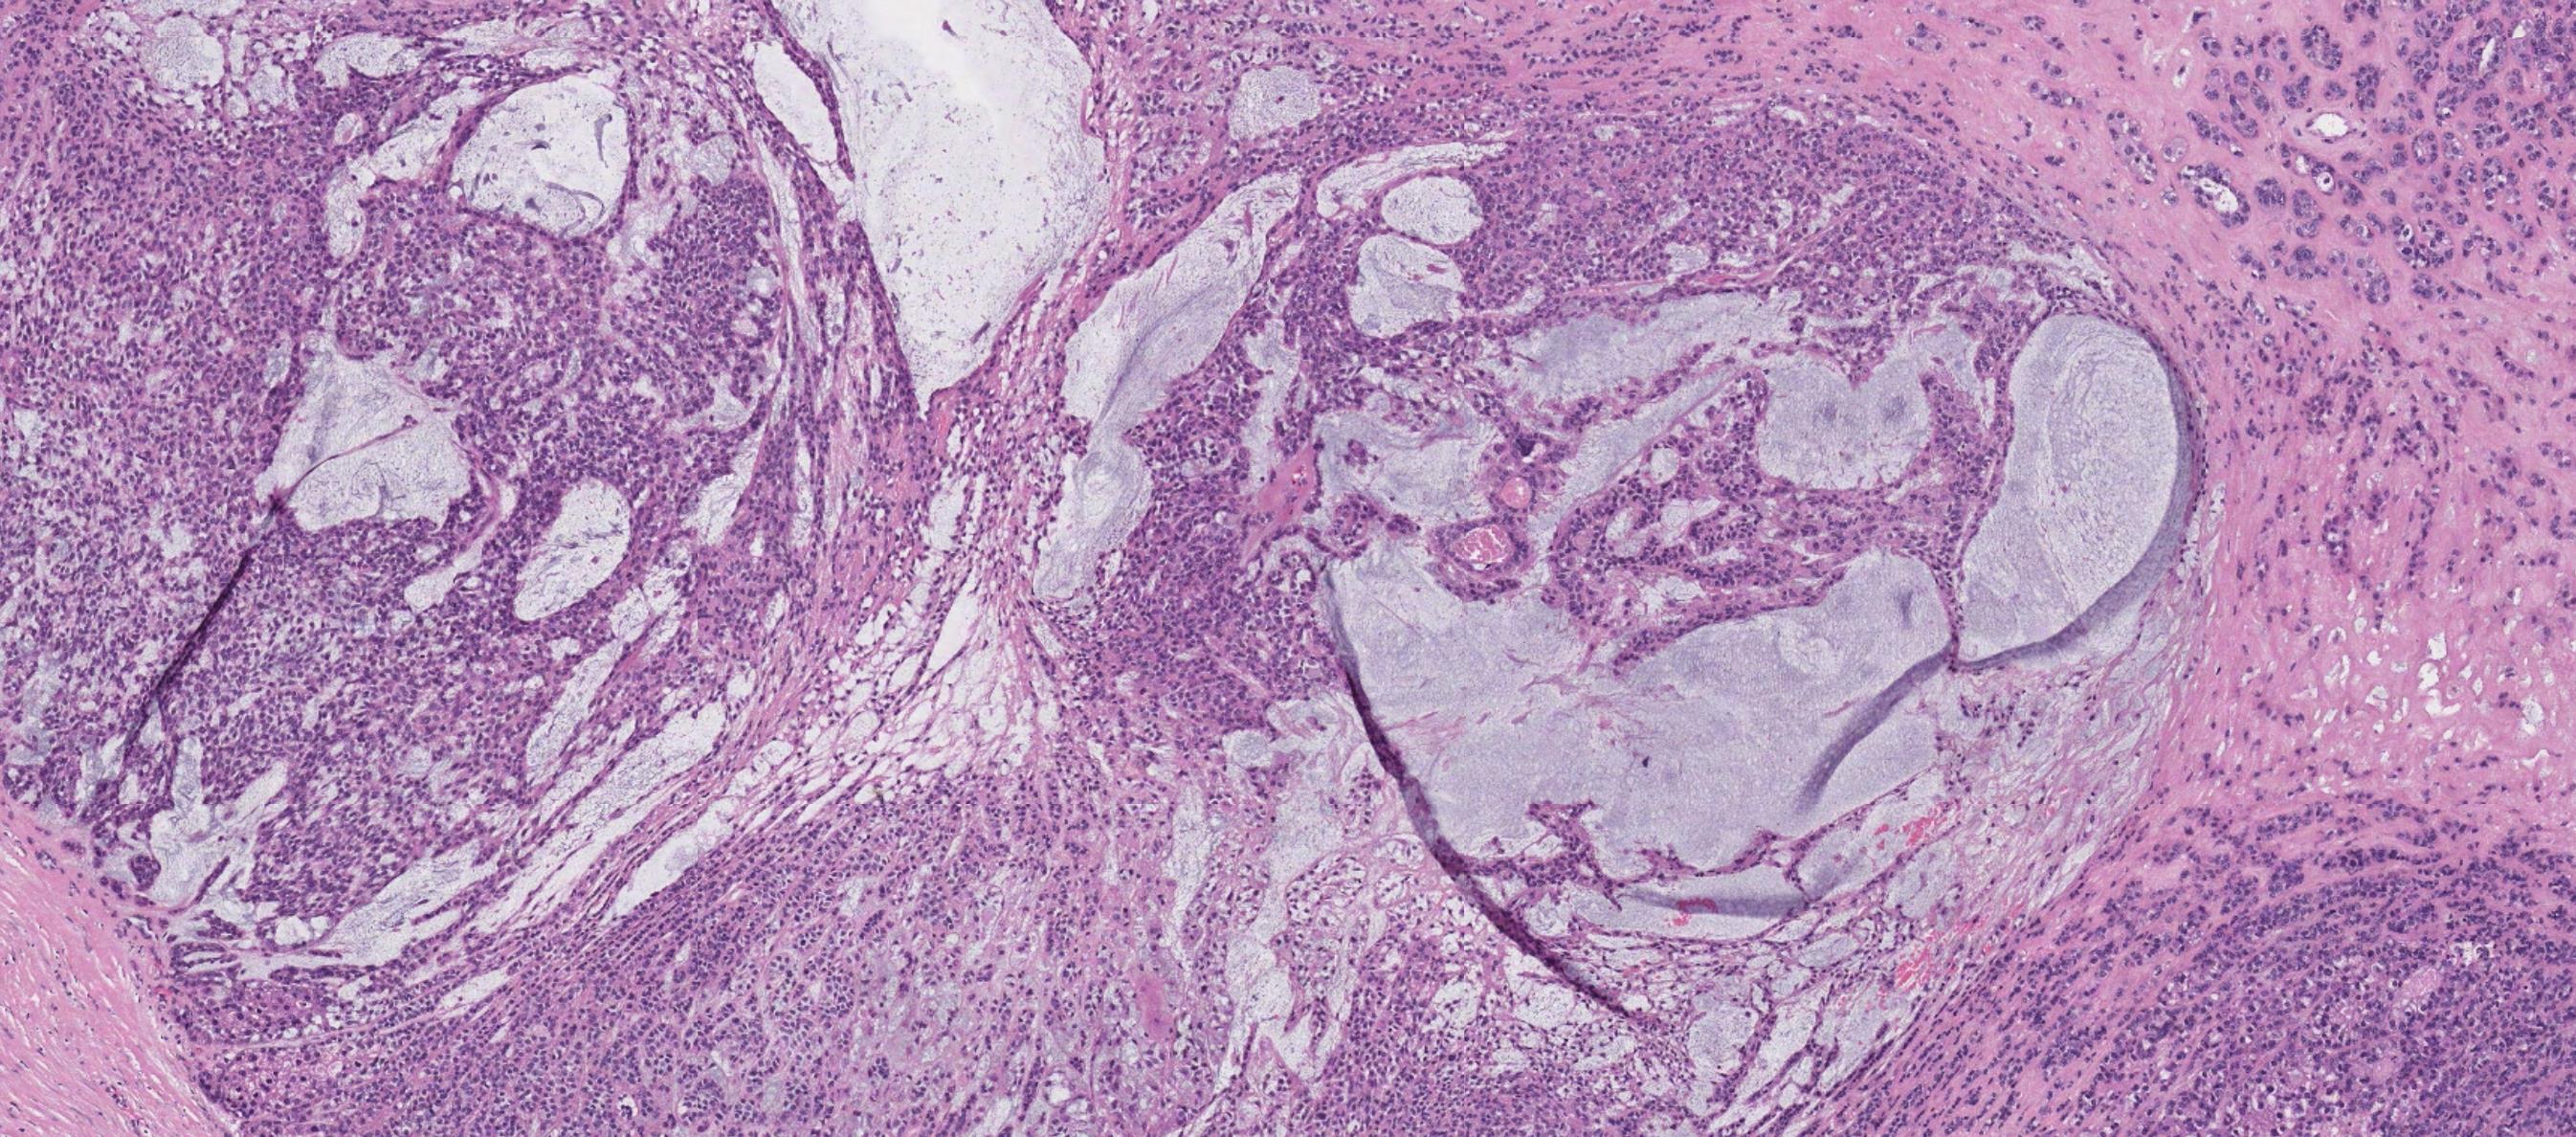

Case 9 Diagnosis

Odontogenic keratocyst

Salient points •Basal cell palisading •Corrugated parakeratosis •Focal inflammation –loss of above and “non-specific” features •Consistent loss of PTCH tumour suppressor gene- GorlinGoltz syndrome •Tendency for recurrence